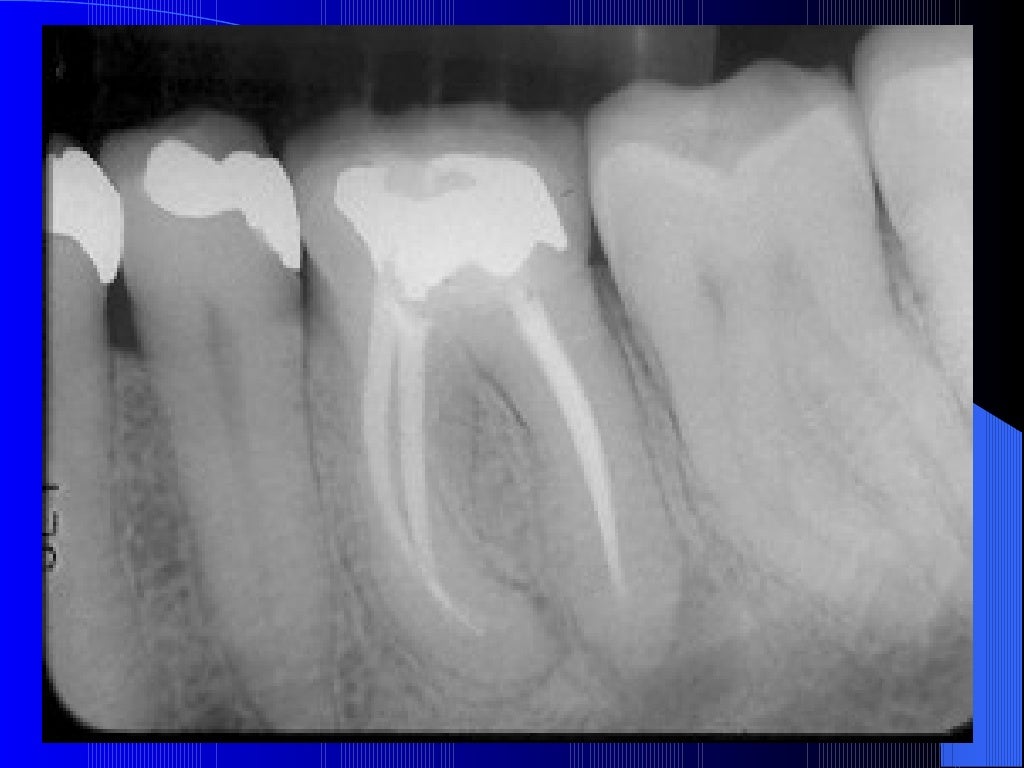

Postendodontic treatment radiograph Download Scientific Diagram Post Endodontic Icd 10 Icd 10 code for endodontic underfill. This article aims to review pain following. Icd 10 code for perforation of root canal space due to endodontic treatment. The diagnosis and management of chronic postendodontic pain are often challenging. M27.51 is a billable diagnosis code used to specify a medical diagnosis of perforation of root canal space due to endodontic treatment. Post Endodontic Icd 10.

OBTURATION AND POST ENDODONTIC RESTORATION DONE Download Scientific

OBTURATION AND POST ENDODONTIC RESTORATION DONE Download Scientific Post Endodontic Icd 10 Icd 10 code for endodontic underfill. Icd 10 code for perforation of root canal space due to endodontic treatment. The diagnosis and management of chronic postendodontic pain are often challenging. M27.51 is a billable diagnosis code used to specify a medical diagnosis of perforation of root canal space due to endodontic treatment. This article aims to review pain following. Post Endodontic Icd 10.